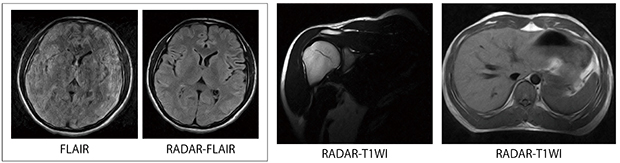

4.RADAR:モーションアーチファクト(画像歪み)低減技術

超電導MRI装置で評価の高いモーションアーチファクト低減技術“RADAR”を搭載しました。MRIのデータ取得を回転状に充填するRadial Scan技術により,アーチファクトの収束を分散し,データの加算効果も期待できます。日立のRADARは,ルーチン検査に使用できる汎用性と良好な画像コントラストが得られることが特長で,永久磁石型MRIの画像はモーションアーチファクトが目立ちにくい性質がありますが,さらにRADARの併用によりアーチファクトの少ない良好な画像を得ることができます。

図3に画像例を示します。頭部の画像は,動きのある被検者に適用した例です。肩関節や腹部の呼吸動にも対応し,呼吸同期のない撮像においても良好な画像が得られます。

図3 RADAR画像例